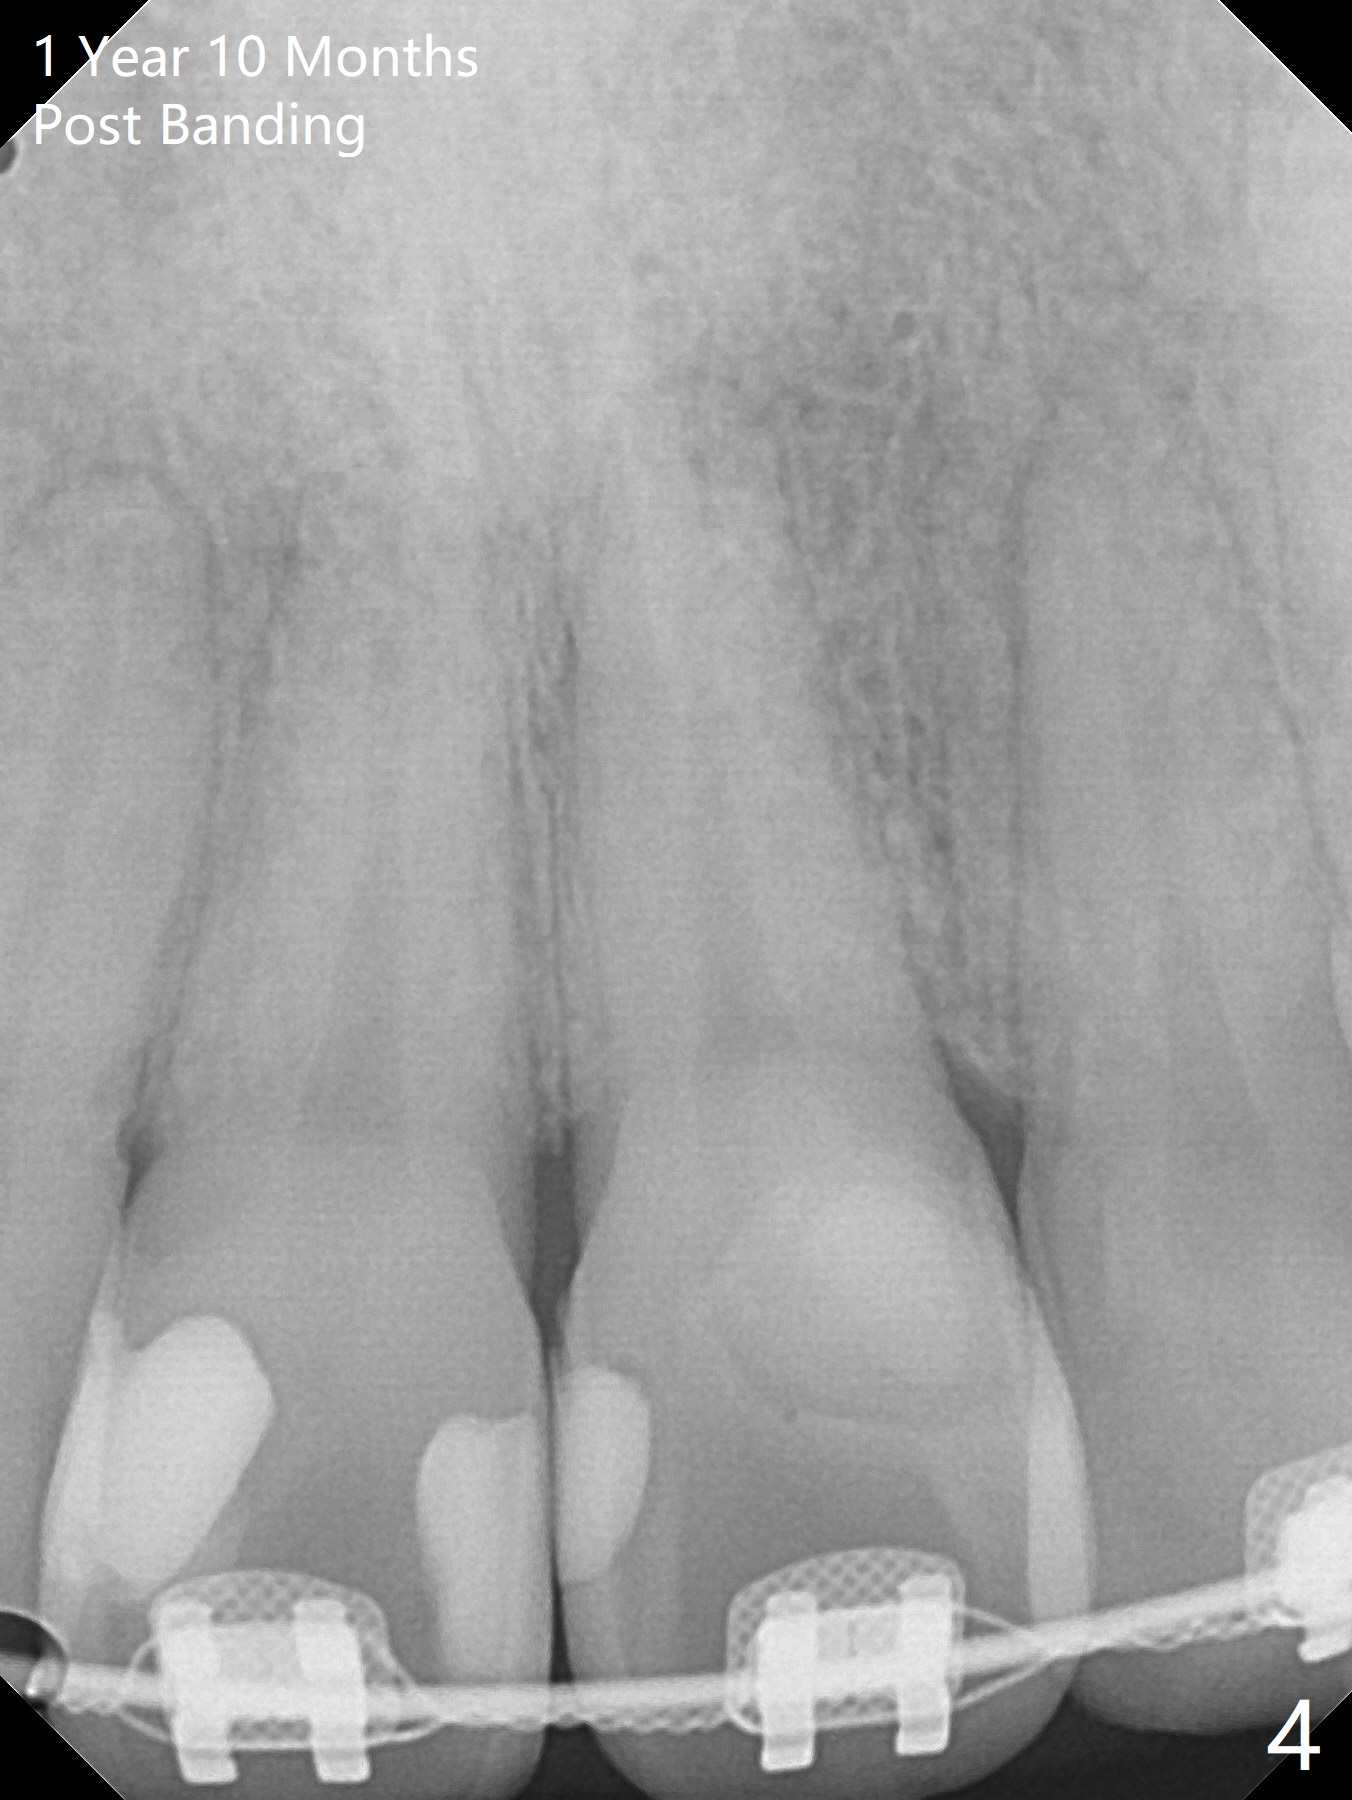

One year 4 months post banding (M) with 16x16 wires, UR3 is being distalized using UR7 as anchor (Fig.1), while the upper dental midline matches the facial one (Fig.2). The anterior overjet remains large (Fig.3). When UR3 is fully distalized, place posted wire to distalize U2-2 together. U2-2 distalization seems to be slow with one 16 mm closed coil spring each side (between 7 and post) 1 year 10 months post banding. Since the upper anterior PA shows mild root resorption at UR2 (Fig.4), a 14 mm closed coil spring is added each side (between 6 and post, Fig.5,6). LR6 has pain 2 years 2 months post banding (Fig.7). Debridement confirms non-salvageability; a 5x11.5 mm implant will be near the mesial root (Fig.8). Power chains for a month leads to closure of the gap between 3 and 4 (Fig.8-11). The space between 4 and 7 is 15 mm. A 12 mm 1st molar crown will be made, while the remaining 3 mm space will be closed by mesialization of 7 using 2 power posts mesial and distal to 6 and 7. Draw 2 tubes of blood. Make an incision to expose the mesial crest of 6.